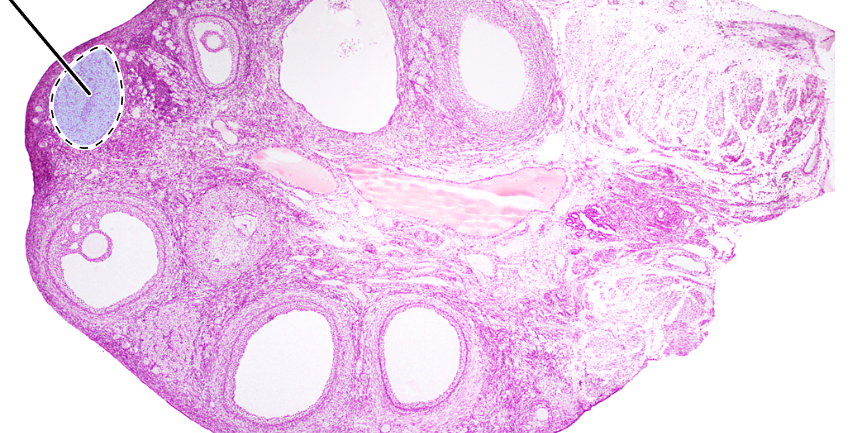

ovary (sagittal section)

primordial follicles

antrum

corona radiata

oocyte

mature tertiary follicle